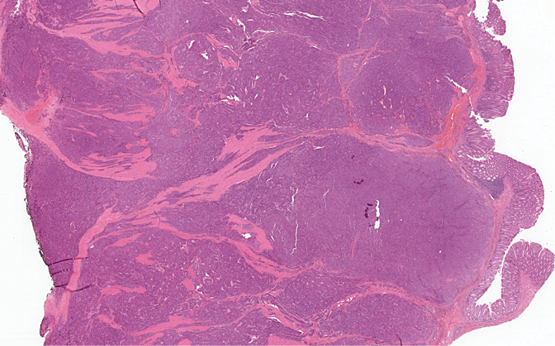

1 pav. Visą storosios žarnos sieną stambiais solidiniais mazgais infiltruojantis navikas (HE 10X)

Mikroskopiniuose preparatuose (1 pav.) matyti infiltratyviai žarnoje plintantis navikas, sudarytas iš trabekulinų, lizdinių ir solidinių struktūrų su pavieniais likutiniais spindžiais, kurias formuoja mišri ląstelių populiacija (2 pav.): dominuoja epitelioidinės kohezyvios ląstelės (apie 40 proc. naviko), pasižyminčios negausia ir vidutinio gausumo eozinofiliška citoplazma, smulkaus ir stambesnio kalibro centruotais, ovaliais arba nelygaus kontūro, polimorfiškais branduoliais. Šeivinės ląstelės sudaro apie 30 proc. naviko, ląstelių citoplazma vidutinio gausumo, eozinofiliška, ląstelėse ištęsti vidutinio kalibro branduoliai. Likusią dalį (apie 30 proc. naviko) sudaro diskohezyvios rabdoidinės išvaizdos ląstelės periferizuotais branduoliais ir ryškiomis nukleolėmis, ekscentriška citoplazma ir eozinofiliniais intracitoplazminiais inkliuzais. Matyti gausios mitozės (40/2 mm2), nekrozės iki 10 proc. naviko tūrio, granuliacinis audinys išopėjusiame paviršiuje. Identifikuotas perineurinis naviko plitimas ir intravaskulinė (smulkių šakų ir intraveninė) invazija; naviko struktūros siekė cirkuliarų rezekcijos kraštą. Antrąjį židinį formavo analogiškos to paties naviko struktūros su negausiu likutiniu limfoidiniu audiniu periferijoje (tikėtina metastazė pasaito limfmazgyje, ekstranodaliai plintanti į žarnos sieną).